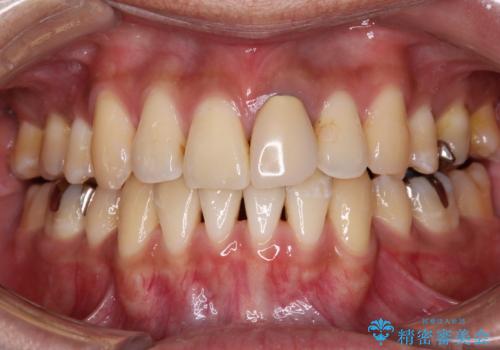

前歯のがたつきをなおしたい マウスピース矯正

担当医 大元洋佑

![[ マウスピース矯正 ] 前歯の角度・がたつきを治したい。の症例 治療前](https://seimitsushinbi.jp/wp/wp-content/uploads/2024/02/IMG_7820-500x350.jpg?v=1707810350)

![[ マウスピース矯正 ] 前歯の角度・がたつきを治したい。の症例 治療後](https://seimitsushinbi.jp/wp/wp-content/uploads/2024/02/8334681fa61954fc45ff8cef14f33166-500x350.jpg?v=1707810480)